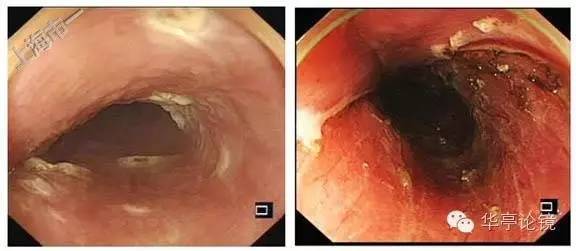

白光内镜:距门齿25cm处食管后壁见片状粘膜浅表凹陷,病灶边缘可见局部隆起,病灶大小约2X1.5cm,提示食管IIc型病变。

碘染色:见病变区片状粘膜脱染。EUS:食道上段粘膜层增厚,累及部分粘膜下层,粘膜下层尚完整,与固有肌层分界清晰。局部壁内可见小淋巴结。

ME-NBI内镜:病变明显处分支血管网消失,IPCL呈IV-V1型改变为主,部分区域呈V2型改变。部分区域粘膜表层糜烂,表浅血管显露(绿色框内)。